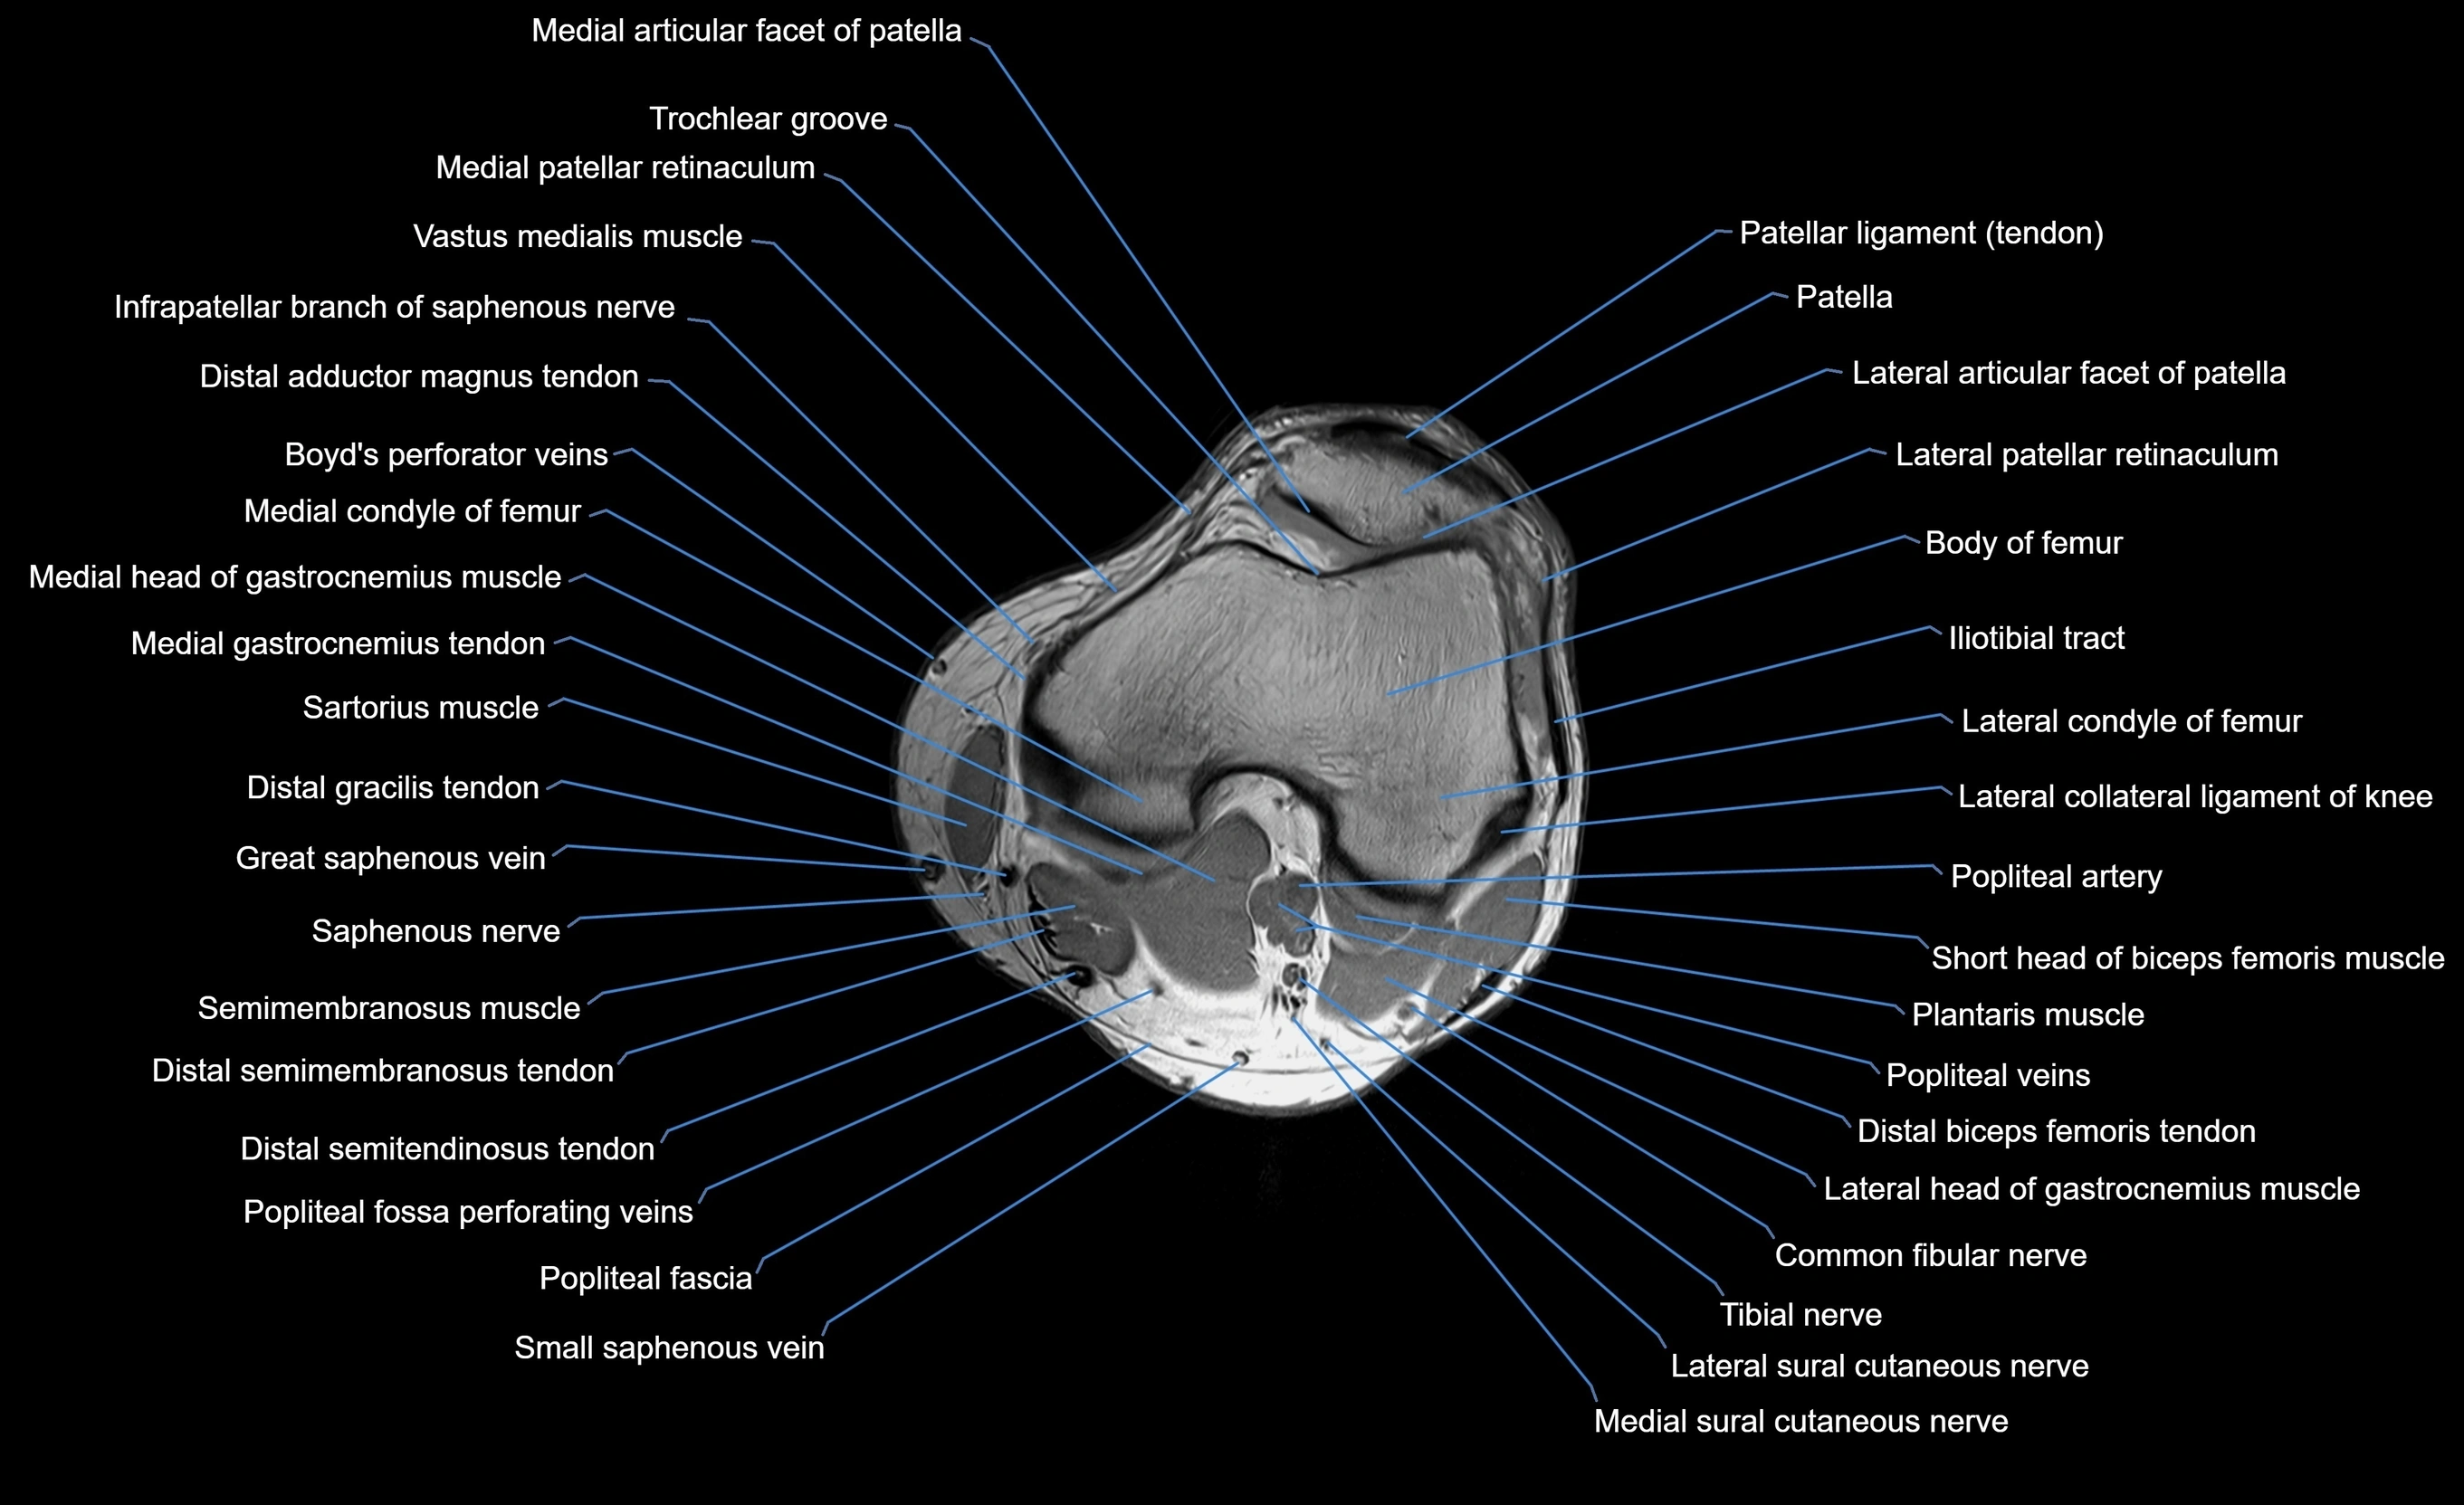

MRI image